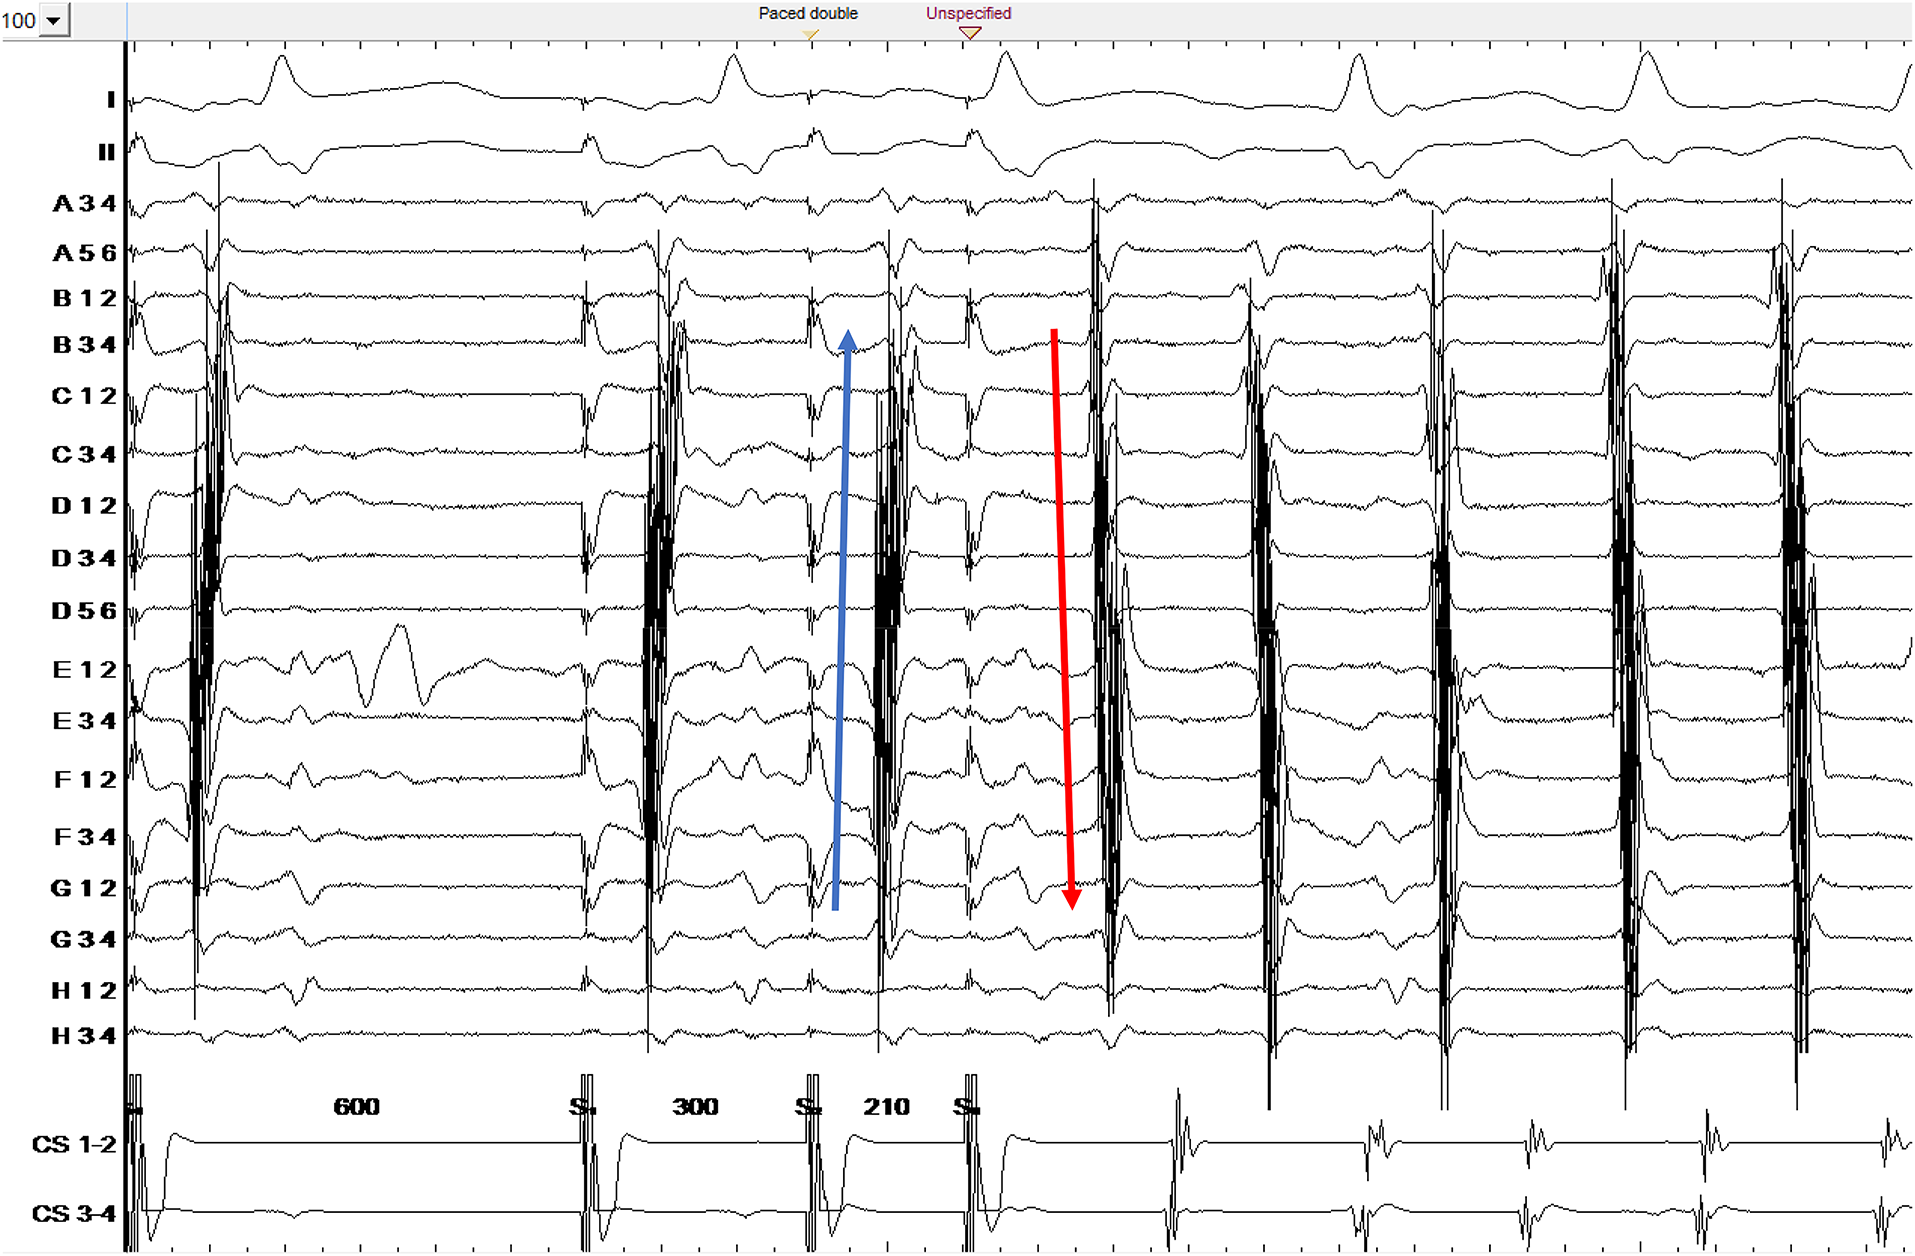

When the map was complete, the S3 beat was further decremented. No additional abrupt changes were observed, until a sequence of 600-300-210 ms at which point CTI-dependent flutter was induced (Figure 1). A map of the flutter was created and compared to the previous maps.

Figure 1

Counterclockwise common atrial flutter induction. Ortaray is positioned at the cavo-tricuspid isthmus level. Note the change in electrogram activation sequence for S3 due to functional block in the septal isthmus region. S3 depicts a unidirectional conduction block on the septal cavo-tricuspid isthmus.

The S3 map shows the additional appearance of a line of block at the septal aspect of the cavo-tricuspid isthmus (Figures 3B,C). The electrogram activation sequence inversion on the Octaray positioned at the CTI level clearly depicts this phenomenon (Figure 1).